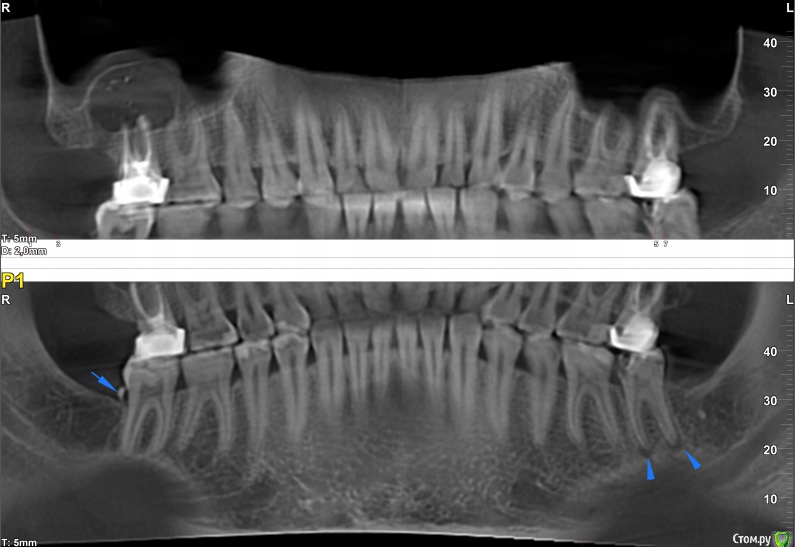

pogoreliy Опубликовано 5 июля, 2017 Автор Поделиться Опубликовано 5 июля, 2017 (изменено) Доброго всем утра. Занимаюсь на данный момент зубом, в рамках чего была сделана КТ. Хотелось бы узнать мнение сообщества о ней. Изменено 5 июля, 2017 пользователем pogoreliy Ссылка на комментарий

Bier Опубликовано 5 июля, 2017 Поделиться Опубликовано 5 июля, 2017 05.07.2016 была сделана та самая панорама, через несколько недель после которой зуб раскрошился. 26.08 мне уже поставили пломбу. Если верить моей, васяпупкинской интерпретации снимков, то кариес до пульпы так и не добрался, чего нельзя сказать о бормашине врача. Разве что микробы совершили трудовой подвиг за эти полтора месяца.на этом панорамном снимке уже есть здоровый кариес. И хр. пульпит. Ссылка на комментарий

Bier Опубликовано 5 июля, 2017 Поделиться Опубликовано 5 июля, 2017 Доброго всем утра. Занимаюсь на данный момент зубом, в рамках чего была сделана КТ. Хотелось бы узнать мнение сообщества о ней.на зубе 3.7 уже периодонтит, т.е. нерв в зубе уже умересть еще проблема на 1.7 - там здоровенная киста. Ссылка на комментарий

pogoreliy Опубликовано 5 июля, 2017 Автор Поделиться Опубликовано 5 июля, 2017 (изменено) Спасибо за внимание! на зубе 3.7 уже периодонтит, т.е. нерв в зубе уже умерА чего у него там, паразита, в таком случае болеть изволит? есть еще проблема на 1.7 - там здоровенная киста.Ну зашибись Это шарик такой грибообразный? Изменено 5 июля, 2017 пользователем pogoreliy Ссылка на комментарий